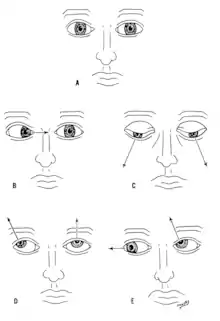

Eye movement (III, IV, VI)

The oculomotor nerve (III), trochlear nerve (IV) and abducens nerve (VI) coordinate eye movement. The oculomotor nerve controls all muscles of the eye except for the superior oblique muscle controlled by the trochlear nerve (IV), and the lateral rectus muscle controlled by the abducens nerve (VI). This means the ability of the eye to look down and inwards is controlled by the trochlear nerve (IV), the ability to look outwards is controlled by the abducens nerve (VI), and all other movements are controlled by the oculomotor nerve (III)[16]

Damage to these nerves may affect the movement of the eye. Damage may result in double vision (diplopia) because the movements of the eyes are not synchronized. Abnormalities of visual movement may also be seen on examination, such as jittering (nystagmus).[17]

Damage to the oculomotor nerve (III) can cause double vision and inability to coordinate the movements of both eyes (strabismus), also eyelid drooping (ptosis) and pupil dilation (mydriasis).[18] Lesions may also lead to inability to open the eye due to paralysis of the levator palpebrae muscle. Individuals suffering from a lesion to the oculomotor nerve may compensate by tilting their heads to alleviate symptoms due to paralysis of one or more of the eye muscles it controls.[17]

Damage to the trochlear nerve (IV) can also cause double vision with the eye adducted and elevated.[18] The result will be an eye which can not move downwards properly (especially downwards when in an inward position). This is due to impairment in the superior oblique muscle.[17]

Damage to the abducens nerve (VI) can also result in double vision.[18] This is due to impairment in the lateral rectus muscle, supplied by the abducens nerve.[17]

A cranial nerve exam starts with observation of the patient, as some cranial nerve lesions may affect the symmetry of the eyes or face.[16] Vision may be tested by examining the visual fields, or by examining the retina with an ophthalmoscope, using a process known as funduscopy. Visual field testing may be used to pin-point structural lesions in the optic nerve, or further along the visual pathways.[17] Eye movement is tested and abnormalities such as nystagmus are observed for. The sensation of the face is tested, and patients are asked to perform different facial movements, such as puffing out of the cheeks. Hearing is checked by voice and tuning forks. The patient's uvula is examined. After performing a shrug and head turn, the patient's tongue function is assessed by various tongue movements.[16]